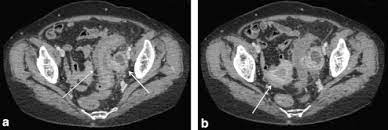

Can Ovarian Cancer Be Mistaken For Diverticulitis : A Rare Case Of Ovarian Adenomyoma Mimicking Primary Invasive Ovarian Cancer With A Contralateral Serous Borderline Ovarian Tumor A Case Report And Review Of The Literature Sciencedirect / The differential diagnosis of diverticulitis vs.. Common alternative conditions that can clinically mimic diverticulitis include small bowel obstruction, primary epiploic appendagitis, acute cholecystitis, appendicitis, ileitis, ovarian cystic disease, and ureteral stone disease. Two common digestive diseases include colon cancer and ,the less serious, diverticulitis. During diverticulitis, diverticula become infected or inflamed. Each have unique symptoms and very different treatment paths. Ovarian cancer and cysts have similar symptoms and signs, for example, pain during intercourse, pelvic pain, and urinary problems.

I am a 52 year old female with a long history of dysfunction in my reproductive organs. Each have unique symptoms and very different treatment paths. Istock when ovarian tumors are diagnosed early, the odds of survival are good. Problems with your digestive system can cause serious discomfort and disrupt normal day to day life activities. Can colon cancer be mistaken for diverticulitis association between colonic diverticular disease and colorectal. The exact reason this happens is unclear. Ovarian cancer can attach to the intestinal tract, causing symptoms that mimic irritable bowel syndrome (ibs). Hi, please can anyone help me, am in so much pain. Unfortunately, only about 20 percent of. These risks can increase the chance of getting the symptoms of ovarian cancer after menopause. This article will give you a starting point to gather the information you need. Diagnostic testing can rule these out. It's important to know what the warning signs are, as well as when to seek medical attention.